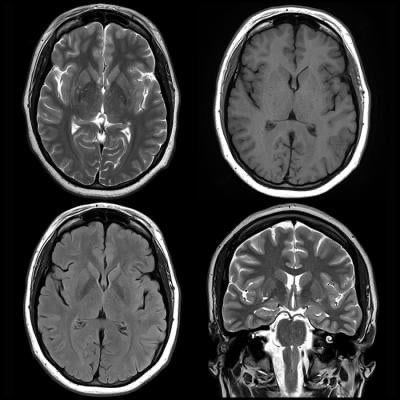

Featured image is from January 2, 2018 — “Information from brain magnetic resonance images (MRIs) can help identify people with attention deficit hyperactivity disorder (ADHD) and distinguish among subtypes of the condition, according to a study appearing online in the journal Radiology.”